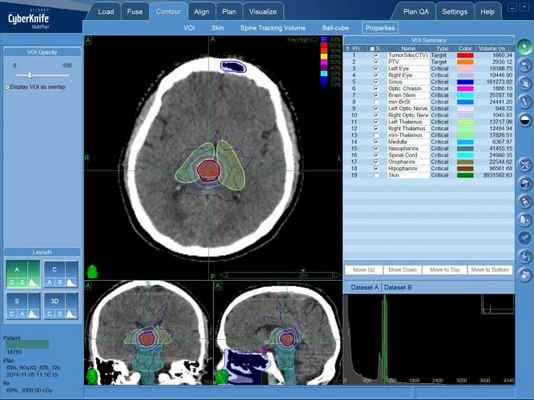

Радиохирургическая система КиберНож

При лечении большинства онкологических заболеваний головного мозга наибольшей эффективности удается достичь с применением радиохирургического метода. Радиохирургия позволяет удалить очаги новообразования в труднодоступных для хирургической операции местах. Поэтому при лечении эпендимомы головного мозга в преимущественно применяется радиохирургия на системе КиберНож.

Лечение на системе КиберНож

В случае раннего диагностирования новообразования, а также небольшого размера опухоли эпендимомы, возможно проведение дистанционного лечения — радиохирургической операции на системе КиберНож.

Для этого в процессе планирования лечения определяется требуемая форма и расположение объема, в котором будет сформирована зона равномерно высокой дозы ионизирующего облучения — она будет полностью совпадать с указанными лечащим врачом контурами опухолевого поражения. Составленная на основе данных КТ- и МРТ-исследований пространственная 3D-модель с указанием зон с минимальной и максимальной лучевой нагрузкой, передается в программный комплекс КиберНожа для расчета множества последовательно подаваемых с различных положений тонких лучей ионизирующего излучения. После этого пациент может начинать лечение эпендимомы на КиберНоже.

Лечение эпендимомы головного мозга на КиберНоже

При радиохирургии на КиберНоже не требуется специальной подготовки пациента, наркоз не проводится — пациент во время фракции (сеанса) лечения эпендимомы на КиберНоже находится в сознании. Роботизированная “рука”-манипулятор комплекса последовательно занимает указанные в плане лечения положения, в каждом из которых производится подача отдельного тонкого пучка ионизирующего излучения. После завершения фракции (15-30 минут) пациент сразу может вернуться к обычному распорядку своего дня. Количество фракций зависит от множества индивидуальных факторов.

Эпендимома головного мозга — план лечения на линейном ускорителе, с распределением доз облучения для различных типов биологических тканей